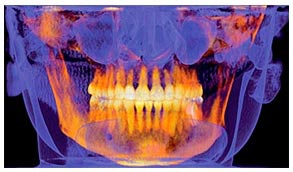

| An image from the GXCB-500 HD cone-beam CT system from Gendex Dental Systems. |

Building on its award-winning 3D design, Gendex Dental Systems introduced the GXCB-500 HD medium field-of-view cone-beam CT system, featuring a high-definition sensor for precise i-CAT-powered 3D scans and detailed 2D pan images. The GXCB-500 HD offers scan flexibility, fast workflow, and integration capabilities. As a result, clinicians can select 3D scans and traditional 2D pans, choose scan sizes specifically designed to work with targeted procedures, and blend technologies for a wide variety of treatment options.